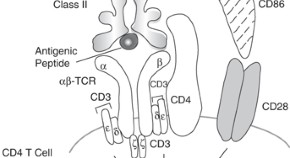

Advances in understanding of B-lymphocyte maturation and immune tolerance are yielding new insight into the influence of gonadal steroids on the humoral immune system. Kovacs and colleagues examine how oestrogens and androgens directly and indirectly modulate B-lymphocyte development and function, focusing on B lymphopoiesis, elimination of autoreactive B-cell clones, and generation of high-affinity, class-switched, immunoglobulin-producing B cells.